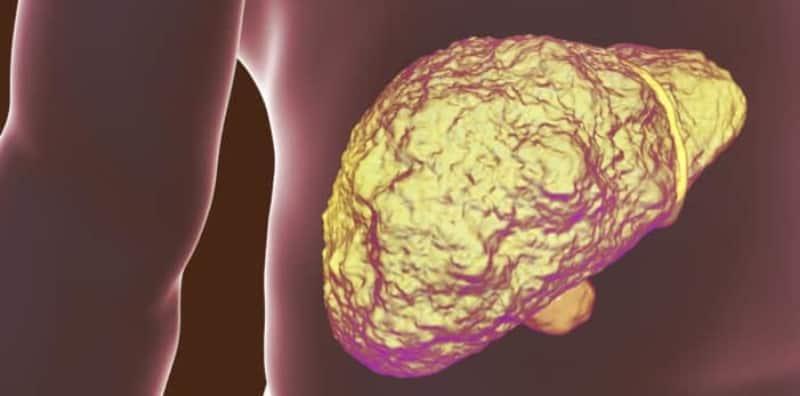

Soal Jawab Doktor: Terambil 3 Biji Paracetamol, Adakah Ia Akan Membahayakan Hati?

Doktor, saya telah termakan ubat paracetamol sebanyak 3 biji. Apakah kesan paracetamol dan adakah ia boleh mendatangkan bahaya kepada hati saya? (matmaryati91-o8v) Soalan diberikan pembaca ini akan dijawab oleh Dr Zai Muhammad Zaidi, Panel Perubatan Hello Doktor. Jawapannya adalah seperti berikut: Untuk mendapatkan lebih banyak info berkenaan Kesihatan, anda boleh klik di sini.